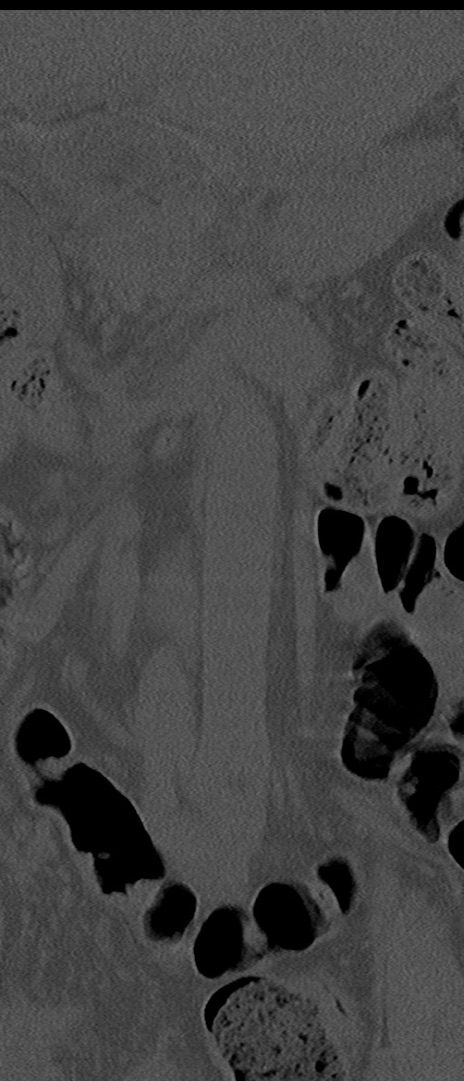

【整形】TIPS症例4 腰椎CT(冠状断像)

腰椎CT